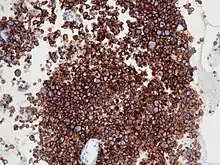

Micrograph of an anaplastic large-cell lymphoma. H&E stain.

Immunohistochemistry for CD30

ALK-positive ALCL is diagnosed by histological and immunological examinations of involved tissues, typically lymph nodes. These tissues have lymphoma-like infiltrates that have variable numbers of ALCL "hallmark" cells, i.e. cells with kidney- or horseshoe-shaped nuclei that strongly express CD30 as detected by immunohistochemistry and an ALK fusion protein as detected by fluorescence in situ hybridization.[11] These cells are scattered throughout the infiltrates. WHO classifies these infiltrates into 5 patterns: a common pattern consisting of large variably shaped cells with large nuclei that typically contain multiple nucleoli (60–70% of cases); a small-cell pattern consisting of small to medium-sized neoplastic cells with clear cytoplasm and "hallmark" cells that are concentrated around small blood vessels (5–10% of cases); a lymphohistiocytic pattern consisting of small neoplastic cells along with abundant histiocytes (10% of cases); a Hodgkin's-like pattern in which the architecture resembles the nodular sclerosis pattern of Hodgkin lymphoma (3% of cases); and a composite pattern consisting of two or more of the just described patterns (15% of cases).[9] Detection of circulating autoantibody against ALK supports the diagnosis.[10] Individuals with low levels of these autoantibodies are at an increase risk of relapsing after treatment.[9]